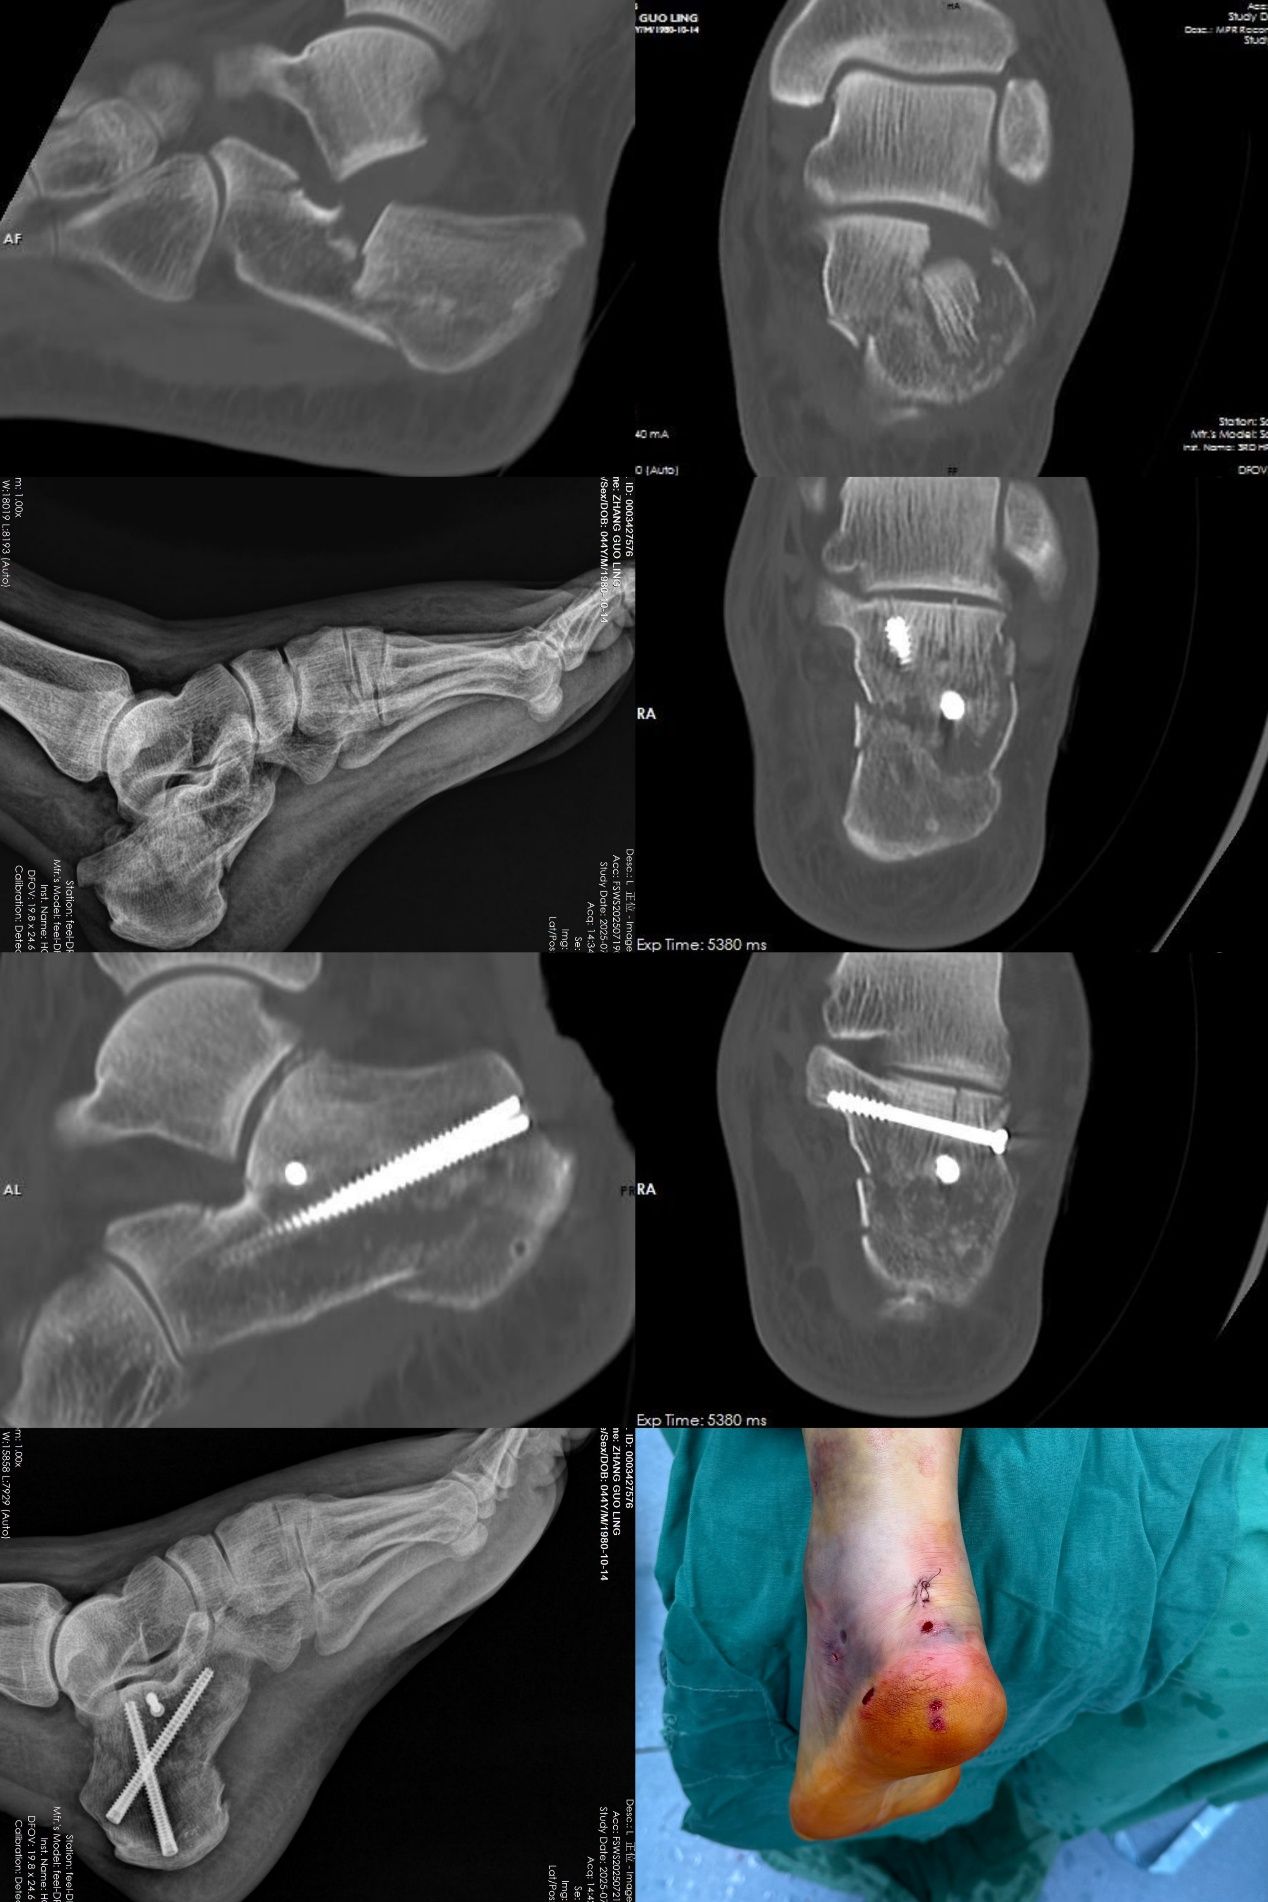

该项微创手术具有多项显著优点。首先,手术无需传统大切口。医生仅通过体表几个如“钥匙孔”般的微小穿刺点,借助特殊器械与术中实时影像引导,在闭合状态下实现骨折块的精准对位,恢复跟骨原有结构。复位后采用经皮植入螺钉完成固定,最大限度保留软组织完整性,使患者可更早开展康复训练。

其次,该手术可降低软组织损伤及相关并发症。手术过程中对肌肉、韧带、血管及神经的影响较小,从而显著减少术后感染、皮肤坏死、伤口愈合不良等常见风险。患者不再需要为并发症过度担忧,康复过程更加顺畅安心。

不仅如此,由于手术创伤小,患者术后疼痛感也明显减轻,可以更早开始踝关节功能锻炼与系统康复。“早活动”是促进骨折愈合、避免关节僵硬、提升功能恢复效果的关键。微创手术让患者能更快、更主动地投入康复训练,整体恢复周期大幅缩短,回归日常生活的速度也明显加快。